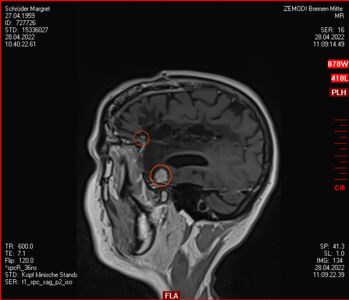

Mai 2022: Schöner Start in den Frühling mit kleinem Fehler

Zu meinem Geburtstag am 27.4. habe ich sehr schöne Geschenke bekommen und kann mich auch über meinen bunten Garten freuen, im Herbst gab es ein Tulpen-Sonderangebot, dem konnte ich nicht wiederstehen! Und nun ist das Ergebnis zu sehen. Am 28. April war wieder mal MRT-Termin. Leider hat es an dem Tag eine Vertretung des auswertenden Arztes gegeben, die Ärztin war super freundlich aber hat keine ganz konkreten Aussagen machen können, aber sie hat mir 2 CDs gebrannt, ich konnte eine gleich bei den Neurochirurgischen Ambulanz abgeben und eine mit nach Hause nehmen. Mein Blick auf die Bilder hat eine nazu unveränderte Lage gezeigt.

Heute war der Termin beim Chirurgen, leider schon um 9:00 Uhr und natürlich wollte ich die knapp 20 km mit dem Rad zurück legen, Stephan wollte gerne mitkommen. Leider war die bereits abgegebenen CD nicht eingelesen worden und so musste erstmal die Datenverarbeitung arbeiten und wir warten, bis wir eine Auskunft bekommen konnten. Fazit: Der bestehende Tumor ist kaum gewachsen. Aber es hat sich leider ein 2. Fund ergeben, sehr klein aber deutlich sichtbar. Aber Maßnahmen sind erstmal nicht notwendig.